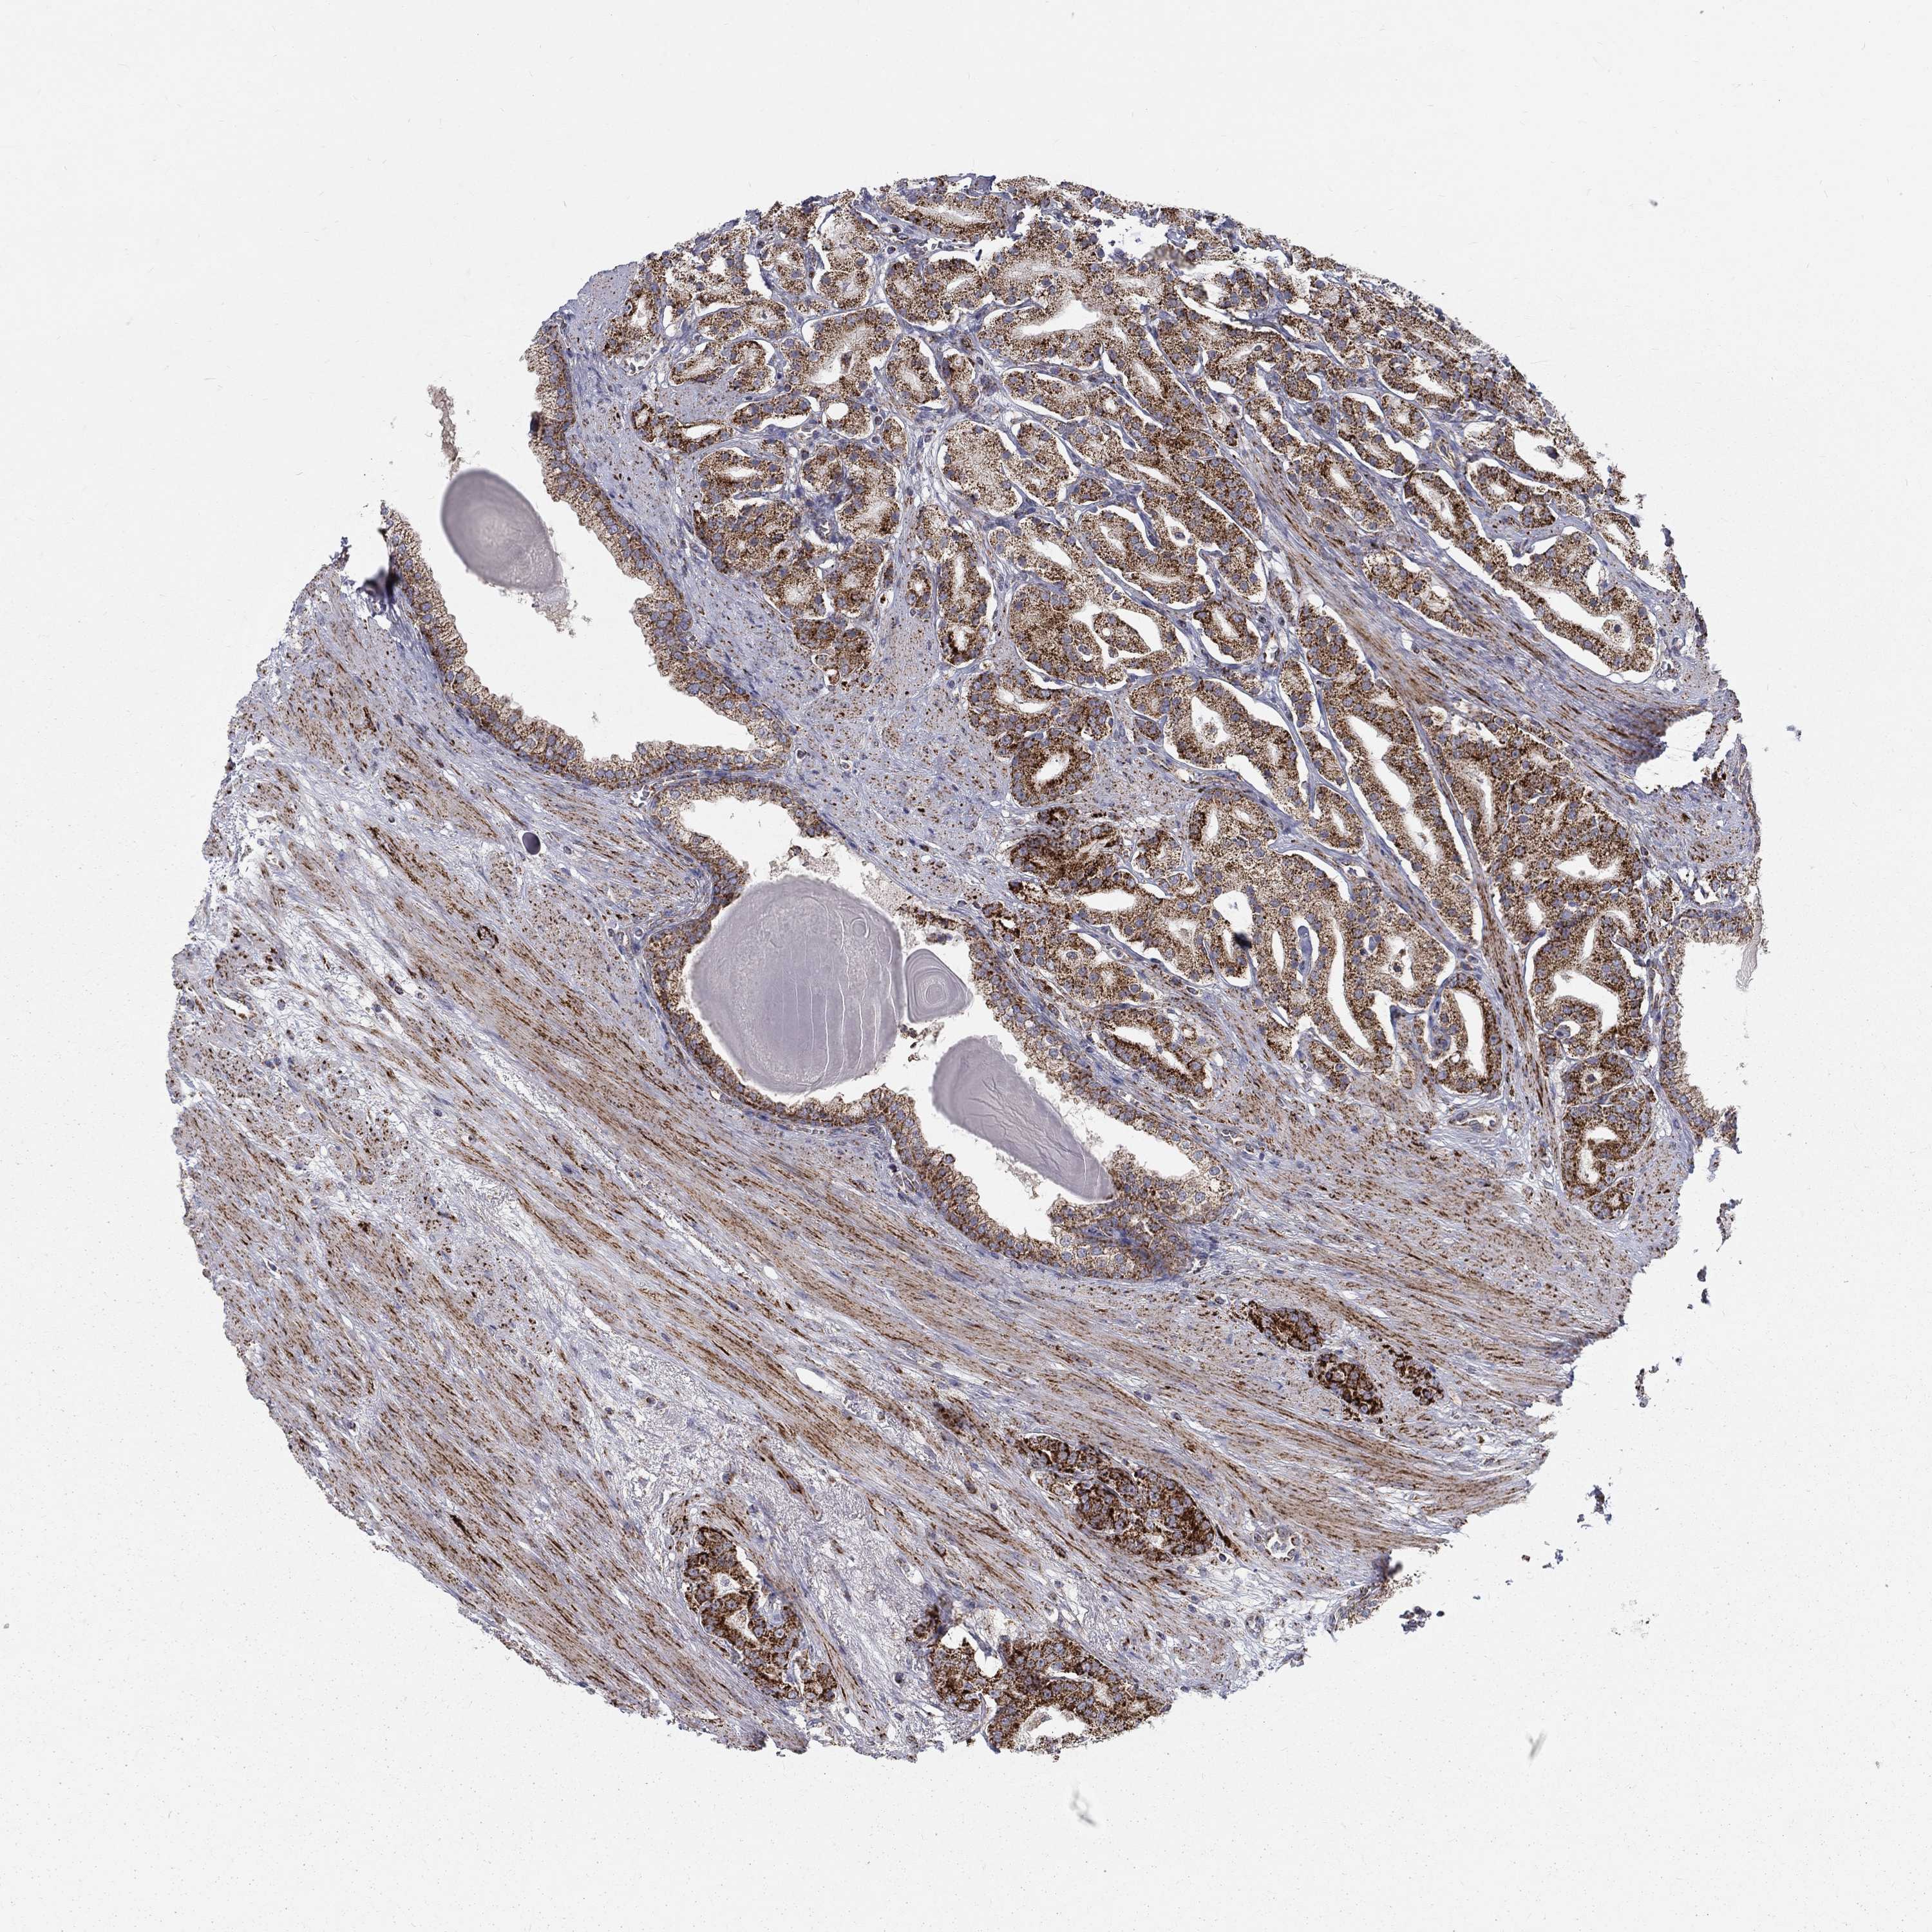

PROSTATE CANCER - Protein expressioni

A mouse-over function shows sample information and annotation data. Click on an image to view it in a full screen mode. Samples can be filtered based on level of antibody staining by selecting one or several of the following categories: high, medium, low and not detected. The assay and annotation is described here.

Note that samples used for immunohistochemistry by the Human Protein Atlas do not correspond to samples in the TCGA dataset.

Antibody stainingi

Antibody staining in the annotated cell types in the current human tissue is reported as not detected, low, medium, or high, based on conventional immunohistochemistry profiling in selected tissues. This score is based on the combination of the staining intensity and fraction of stained cells.

Each image is clickable and will lead to virtual microscopy that enables deeper exploration of all samples and also displays staining intensity scores, fraction scores and subcellular localization as well as patient and tissue information for each sample.

Antibody HPA021037

Antibody HPA077080

Staining

High

Medium

Low

Not detected

Intensity

Strong

Moderate

Weak

Negative

Quantity

>75%

75%-25%

<25%

None

Location

Nuclear

Cytoplasmic/membranous

Cytoplasmic/membranous,nuclear

Adenocarcinoma, High grade

Adenocarcinoma, Low grade

Adenocarcinoma, Medium grade

Adenocarcinoma, NOS